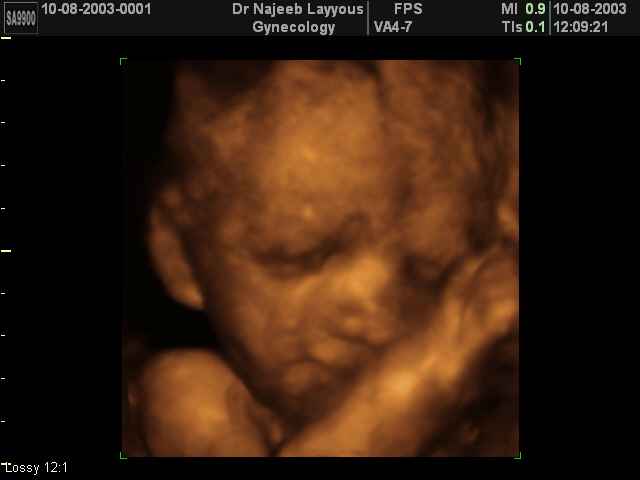

- Fetal Behavior Ultrasound Photos

Ultrasound Photos in 3D showing Fetal Behavior Inside the uterus | Dr N Layyous